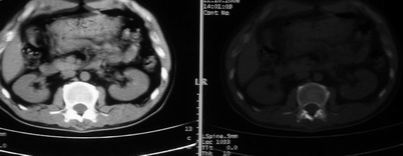

以下是引用余辉在2008-10-23 16:14:00的发言:[br]腰椎体棱角分明,小关节退变部分隔合,骶髂关节部分融合,考强脊炎